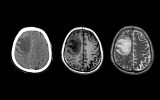

Выяснилось, что происходит с мозгом при ожирении